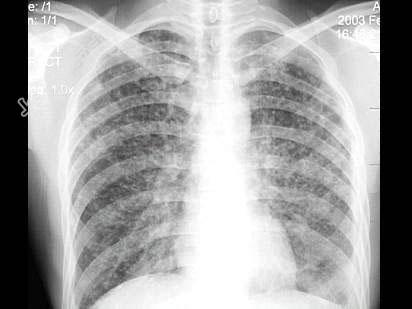

- 单项选择题男,24岁, 低热、乏力数周,夜间偶有盗汗, 胸片如图,最可能的诊断是 ( )

D、血型播散型肺结核